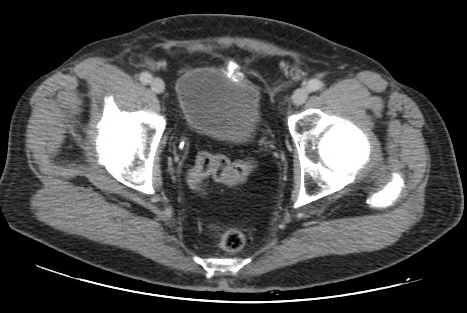

A 77-year-old patient with history of non muscle invasive and recurrent multifocal bladder tumour (pTaG2), with superficial 4-mm recurrence in the fundus bladder mucosa during the follow-up, underwent a transurethral resection of bladder tumor (TURB). Without bladder perforation suspected, intravesical instillation Mitomycin-C in the immediate postoperative period was administered. In cystoscopy, 3 months later, with the patient being asymptomatic, a fibrino-stone like growing was observed, arising from fundus bladder mucosa (1, 2). In an attempt to dismiss a post TURB leak, a biopsy of the fibrinous material was taken and URO-CT performed, which revealed irregularity and a scar tract with some calcifications within the bladder anterior wall (Fig.1 and Fig.2). The histological result of the sample taken was adipose tissue, necrosis, lymphoplasmacytic inflammatory infiltrate and dystrophic calcifications (3), compatible with encrusted cystitis. With those findings in the anatomopathological report, urine sample was analyzed. The pH of the urine was 6 and the culture was negative, so encrustated cystitis was dismissed (4). Most probable, the changes in the bladder mucosa were due to a reactive process to the intravesical instillation of Mytomicin-C in a non-suspected microscopic perforation of bladder wall. During the follow-up after biopsy, the patient was asymptomatic and without pathological findings in the cystoscopy.